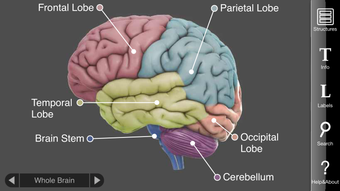

Usando a tela sensível ao toque, os usuários podem girar e ampliar em torno de 29 estruturas cerebrais interativas. Cada estrutura fornece informações detalhadas sobre suas funções, distúrbios, danos cerebrais, estudos de caso e links para pesquisas modernas. Essas informações abrangentes ajudam os usuários a entender como cada região cerebral funciona, o que acontece quando ela é lesionada e como ela está envolvida em doenças mentais.